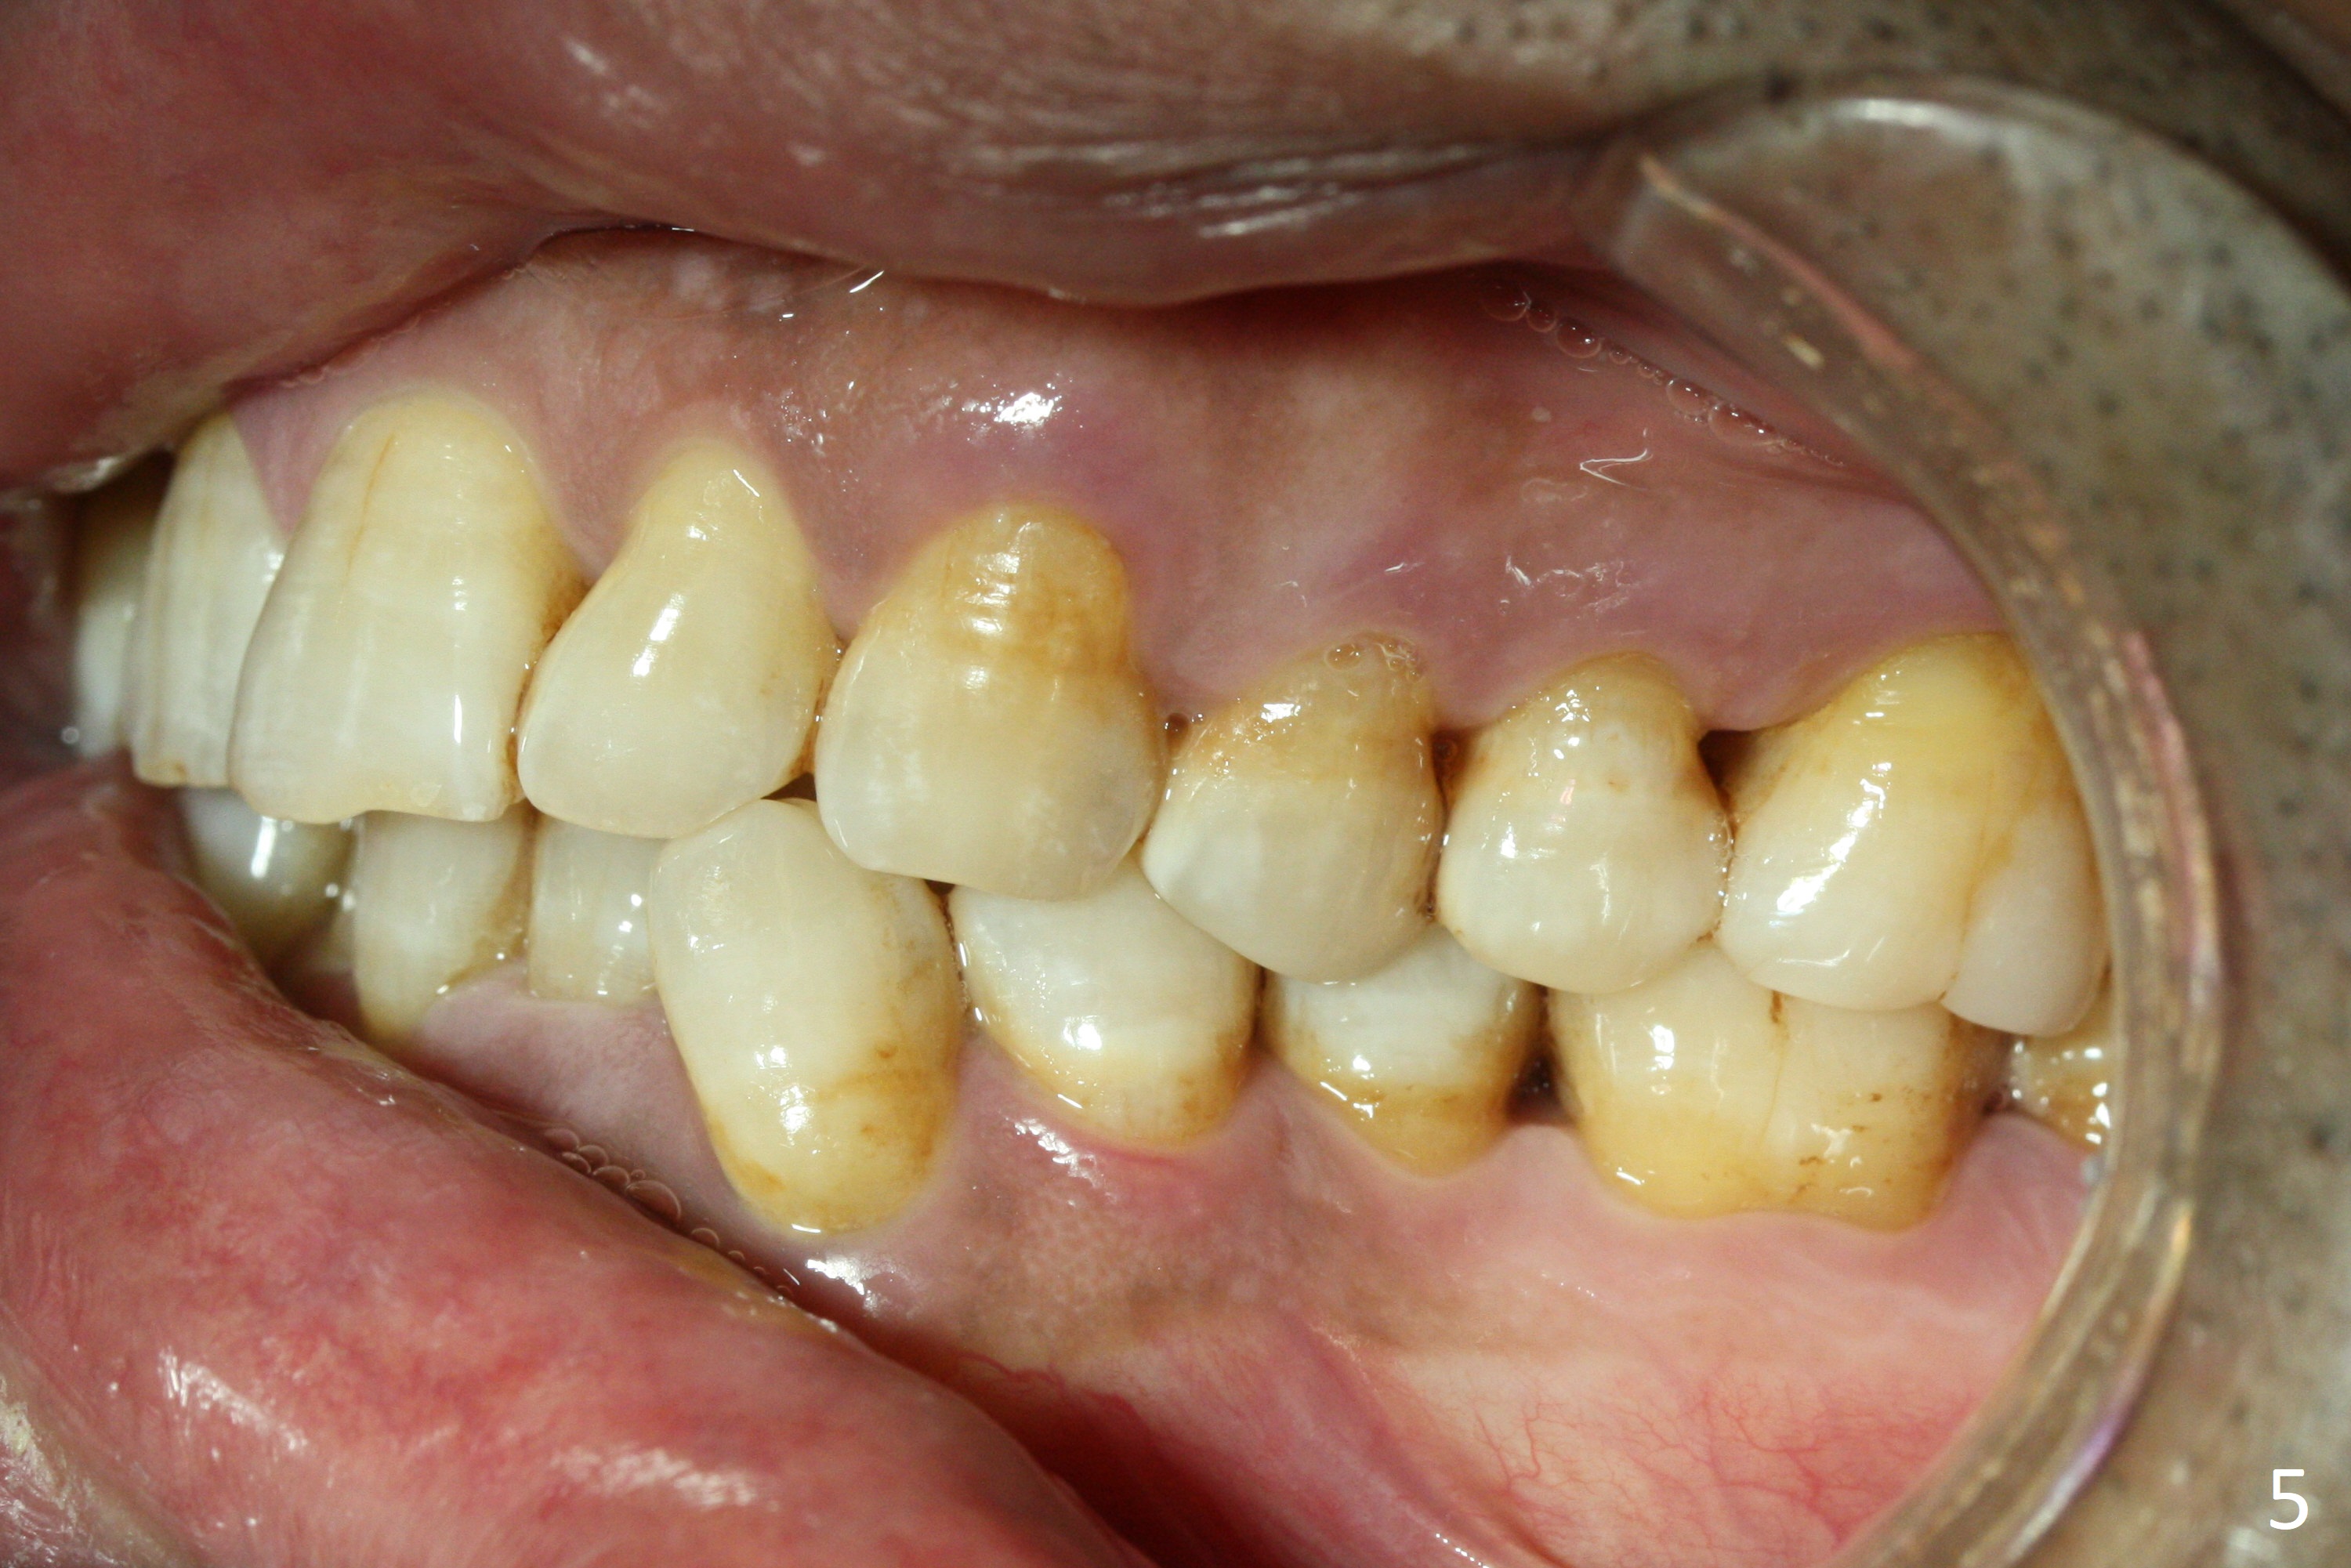

Enough Space For Crowding After Extraction? A 47-year-old man requests orthodontic treatment following SRP in other office (Fig.1-11). For severe crowding and midline shifting, extraction of four of the 1st bicuspids is imminent. Is it enough? To answer the question, model surgery is performed (Fig.12-16). 1st visit: periodontal maintenance, orthodontic consent (emphasizing oral hygiene) extract 4s and possibly L8s and separators. The beauty of this vist is that after local anesthesia and extraction including L8s, it is painless and easy to remove calculus from the proximal surfaces of the neighboring teeth. It is much easier to place separators after extraction. It is expected that there is no gingival erythema when the patient returns for bracketing. Take photos of UR3, similar to Fig.3. Molar banding is also anticipated to be easy with separator placement after extraction. Return to Ortho Cases Xin Wei, DDS, PhD, MS 1st edition 11/23/2017, last revision 04/28/2019